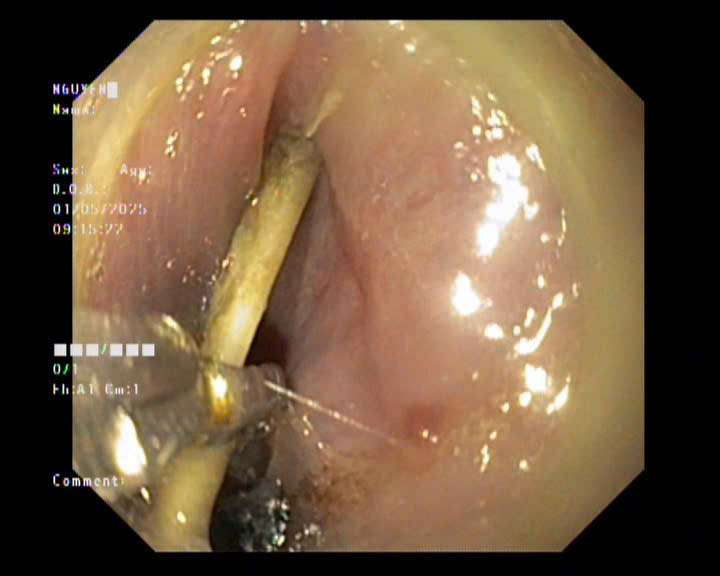

Hình 1: Dị vật thực quản

Ngày 25/5/2025, Khoa Thăm dò chức năng tiếp nhận một bệnh nhân cao tuổi với nhiều bệnh lý nền (tăng huyết áp, đái tháo đường), đến viện trong tình trạng đau rát dữ dội vùng cổ ngực sau ăn chim bồ câu. Qua khai thác bệnh sử và nội soi tiêu hóa cấp cứu, phát hiện dị vật là xương lớn, sắc nhọn, mắc ngang thực quản đoạn 1/3 trên, đầu xương cắm vào thành thực quản, nguy cơ gây thủng hoặc áp xe trung thất nếu xử trí không kịp thời. Ekip gồm các bác sĩ nội soi và bác sĩ gây mê – hồi sức giàu kinh nghiệm đã nhanh chóng hội chẩn, tiến hành nội soi can thiệp gắp dị vật dưới gây mê tĩnh mạch toàn thân. Với thao tác khéo léo và sự phối hợp nhịp nhàng, dị vật được lấy ra an toàn sau vài phút, không để lại tổn thương niêm mạc đáng kể. Bệnh nhân hồi phục tốt, ăn nhẹ sau 6 giờ và được xuất viện trong ngày, tiếp tục theo dõi tại nhà.